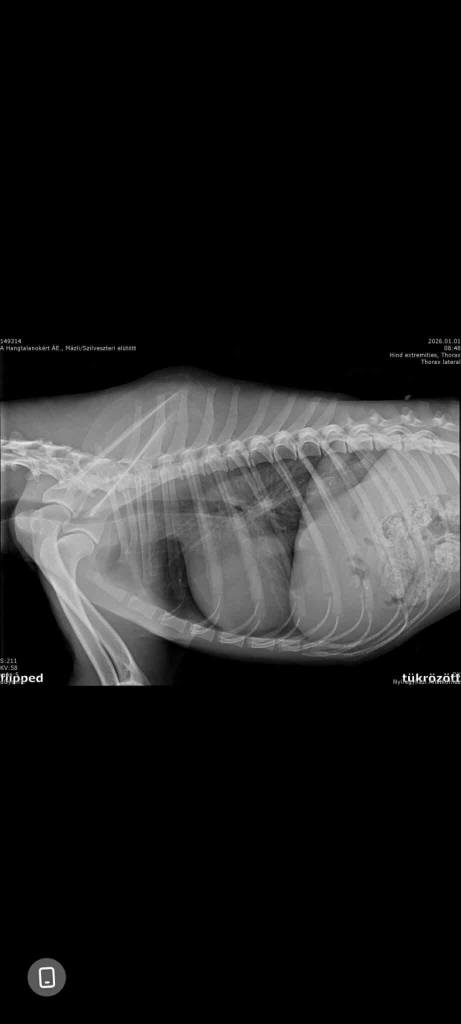

. Mázli hatte in der Tat Glück, dass er gefunden wurde und Hilfe bekam. Glück, dass es bei einem Schienbeinbruch blieb! Der junge Rüde wurde am 31.12 von einer Mitarbeiterin des Tierheims auf der Straße gefunden und durfte die Nacht bei ihr Zuhause im Warmen verbringen. Am Donnerstag kam er in die Tierklinik, wo der besagte Schienbeinbruch diagnostiziert wurde. Zum Glück hat er keine inneren Blutungen. Gechipt ist er allerdings auch nicht. Naheliegend ist, dass Mázli mit einem Auto kollidiert ist.